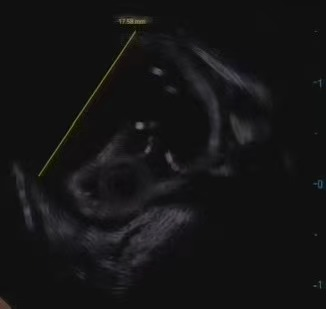

为看清这枚「土豆」的真面目,付先生接受了超声内镜和胸部增强 CT 检查。结果令医生警惕:肿瘤起源于食管深层的「固有肌层」,位于主动脉弓下方和升降主动脉之间,也就是说,在操作治疗时,极有可能出现损伤大血管而出现大出血危及生命的情况!「好比在心脏大血管边上拆弹,操作空间狭小,风险一触即发。」杨叶医生说。